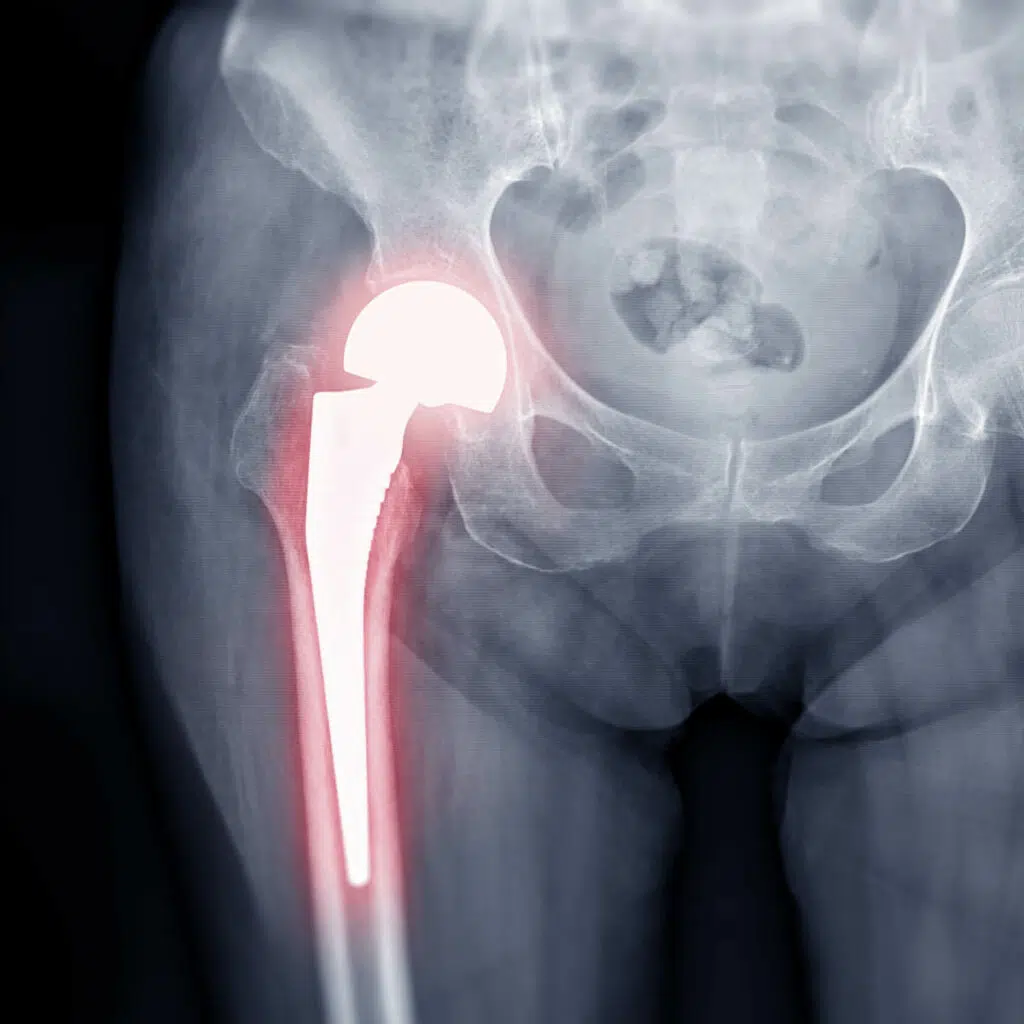

Ein künstliches Hüftgelenk setzen Ärzte vor allem bei Arthrose ein – speziell in der Hüfte auch Coxarthrose genannt. Der Eingriff zählt zu den häufigsten Operationen.1)

© Anatomy Insider | shutterstock.com

4. Was passiert bei einer Operation?

Der Eingriff für ein künstliches Hüftgelenk wird unter Vollnarkose durchgeführt. Das Hüftgelenk können Chirurgen auf unterschiedlichen Wegen erreichen: von vorne, von der Seite durch die Ansätze der Oberschenkelmuskulatur hindurch oder durch den großen Gesäßmuskel von hinten.

Hat der Arzt das Gelenk freigelegt, kommt eine elektrische Säge zum Einsatz, die den Oberschenkelhals samt Hüftkopf vom restlichen Knochen absägt. Anschließend wird die Hüftpfanne so weit ausgefräst, bis es die für das Implantat benötigte Form hat. Als Nächstes wird die Metallaußenschale der Hüftpfanne in das Becken gepresst, wo sie mit der Zeit festwächst.

Nun höhlt der Operateur den Oberschenkelknochen so aus, dass er den Prothesenschaft einsetzen kann. In der Praxis ist das eine brachiale Angelegenheit, denn der Schaft wird regelrecht „eingehämmert”. Als Letztes wird der Gelenkkopf auf den Schaft gesteckt, ehe Muskeln und Haut vernäht werden. Ein Röntgenbild zeigt, ob das Implantat auch wirklich am richtigen Platz sitzt. Nach 15 bis 20 Jahren muss der Hüftgelenkersatz dann in einer Wechseloperation wieder ausgetauscht werden.